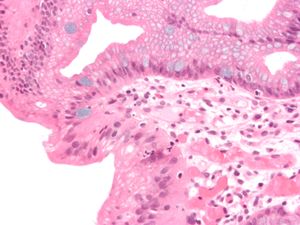

진단을 내리기 위해서는 육안적(내시경 검사) 및 현미경적 양성 소견이 모두 필요하다. 바렛 식도는 정상적인 편평 세포 상피를 대체하는 하부 식도에 원주 상피의 존재로 특징지어진다. 이는 화생의 예시이다. 분비성 원주 상피는 위액의 침식 작용을 더 잘 견딜 수 있지만, 이러한 화생은 선암종의 위험을 증가시킨다.[15]

바렛 식도 진단에는 내시경 검사를 통한 육안적 소견과 현미경을 이용한 조직학적 소견이 모두 필요하다. 바렛 식도는 하부 식도에서 정상적인 편평 세포 상피가 원주 상피로 대체되는 화생 현상이다. 분비성 원주 상피는 위산에 의한 손상에 더 강하지만, 선암 발생 위험을 높인다.[15]치료에도 불구하고 역류 증상이 오래 지속되는 60세 이상 남성은 선별 내시경 검사를 받는 것이 좋다.[16] 예상 생존 기간이 5년 미만인 경우에는 선별 검사가 권장되지 않는다.[16]

조직학적, 병리학적 정의에 따르면, 바렛 식도는 "식도 내 장상피화생을 동반한 원주상피"로 정의되며, 원주상피화생과 점막근판의 2층화가 특징이다.

조직학적, 병리학적인 정의로는 "바렛 식도(Barrett's esophagus)란 식도 내에 존재하는 원주상피로 장상피화생을 동반한 것"으로 정의된다. 원주상피화생과 점막근판의 2층화를 특징으로 한다. 위식도 역류 질환(GERD)에 의해 발생하며, 위산과 십이지장액이 모두 관련되어 있는 것으로 알려져 있다.